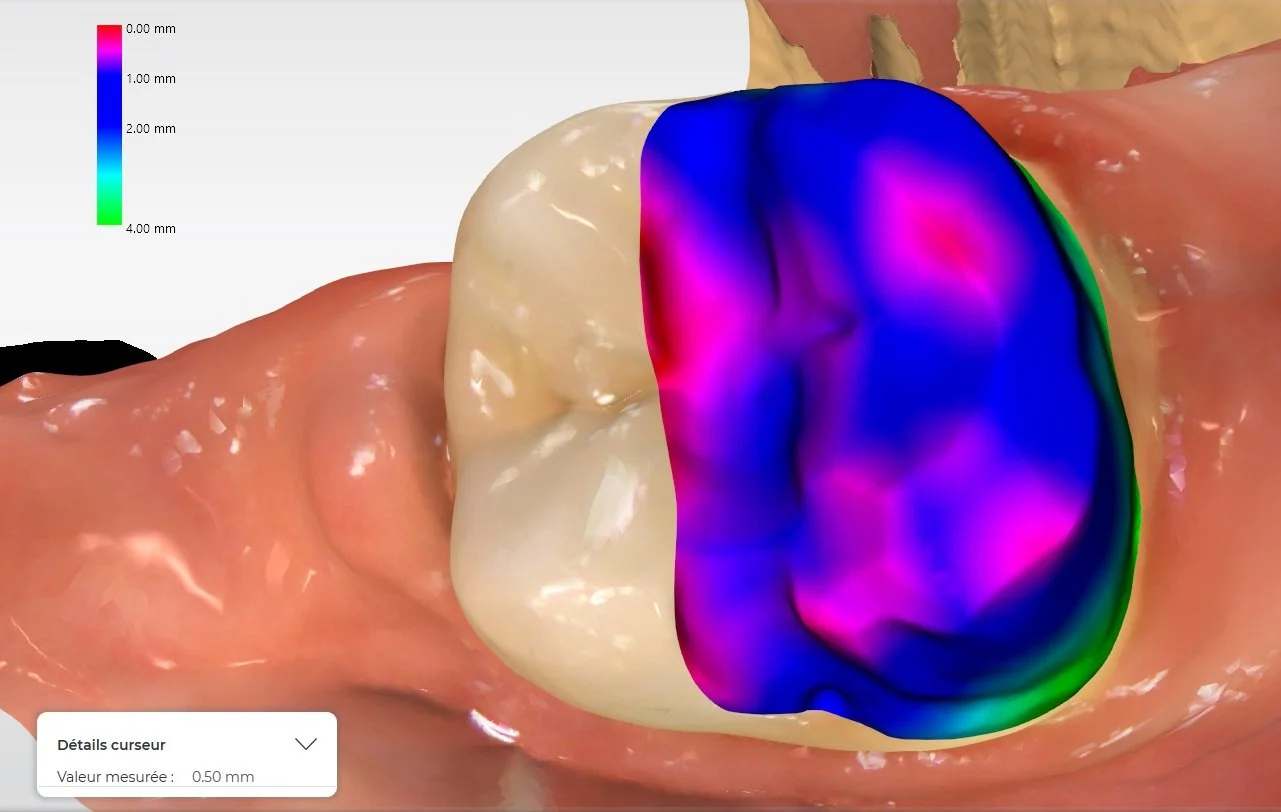

Relativement récents, les bridges collés cantilever postérieurs constituent une alternative fixe, fiable et véritablement minimalement invasive aux implants dans les secteurs postérieurs. Cette thérapeutique qui repose sur des indications bien précises est parfois débattue avec passion sur les réseaux sociaux ou dans les congrès scientifiques. Cependant des études cliniques existent, tout comme des recommandations validées dans des journaux internationaux. Leur succès repose sur des préparations et des principes biomécaniques rigoureux, pourtant simples à intégrer au quotidien. Cette intervention propose un guide clair et opérationnel incluant indications, étapes clés, protocoles d’adhésion et réglages occlusaux pour les mettre en œuvre avec confiance et reproductibilité.